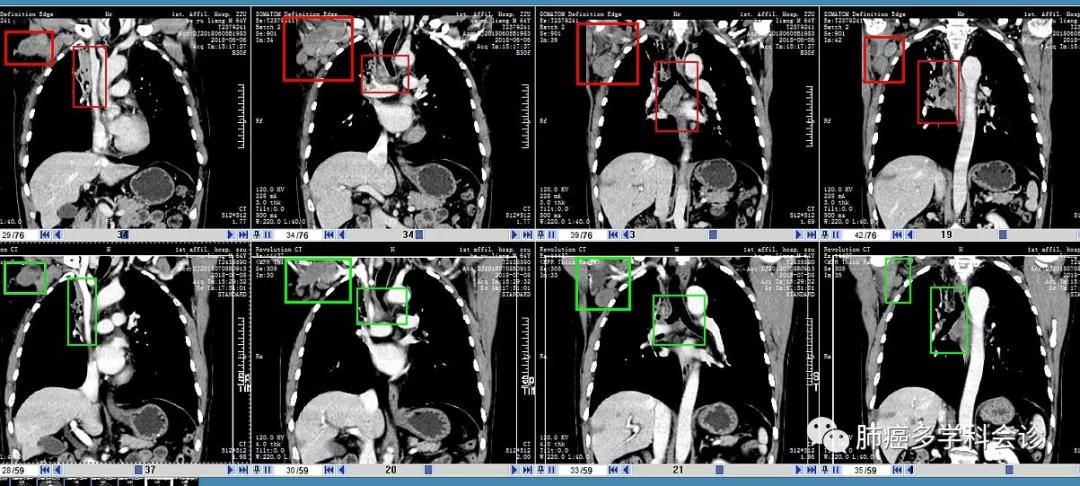

以下是2周期治疗前(每图上行,2018-06-06)和治疗后(每图下行,07-08)腋窝和纵隔转移淋巴结大小等的比较: